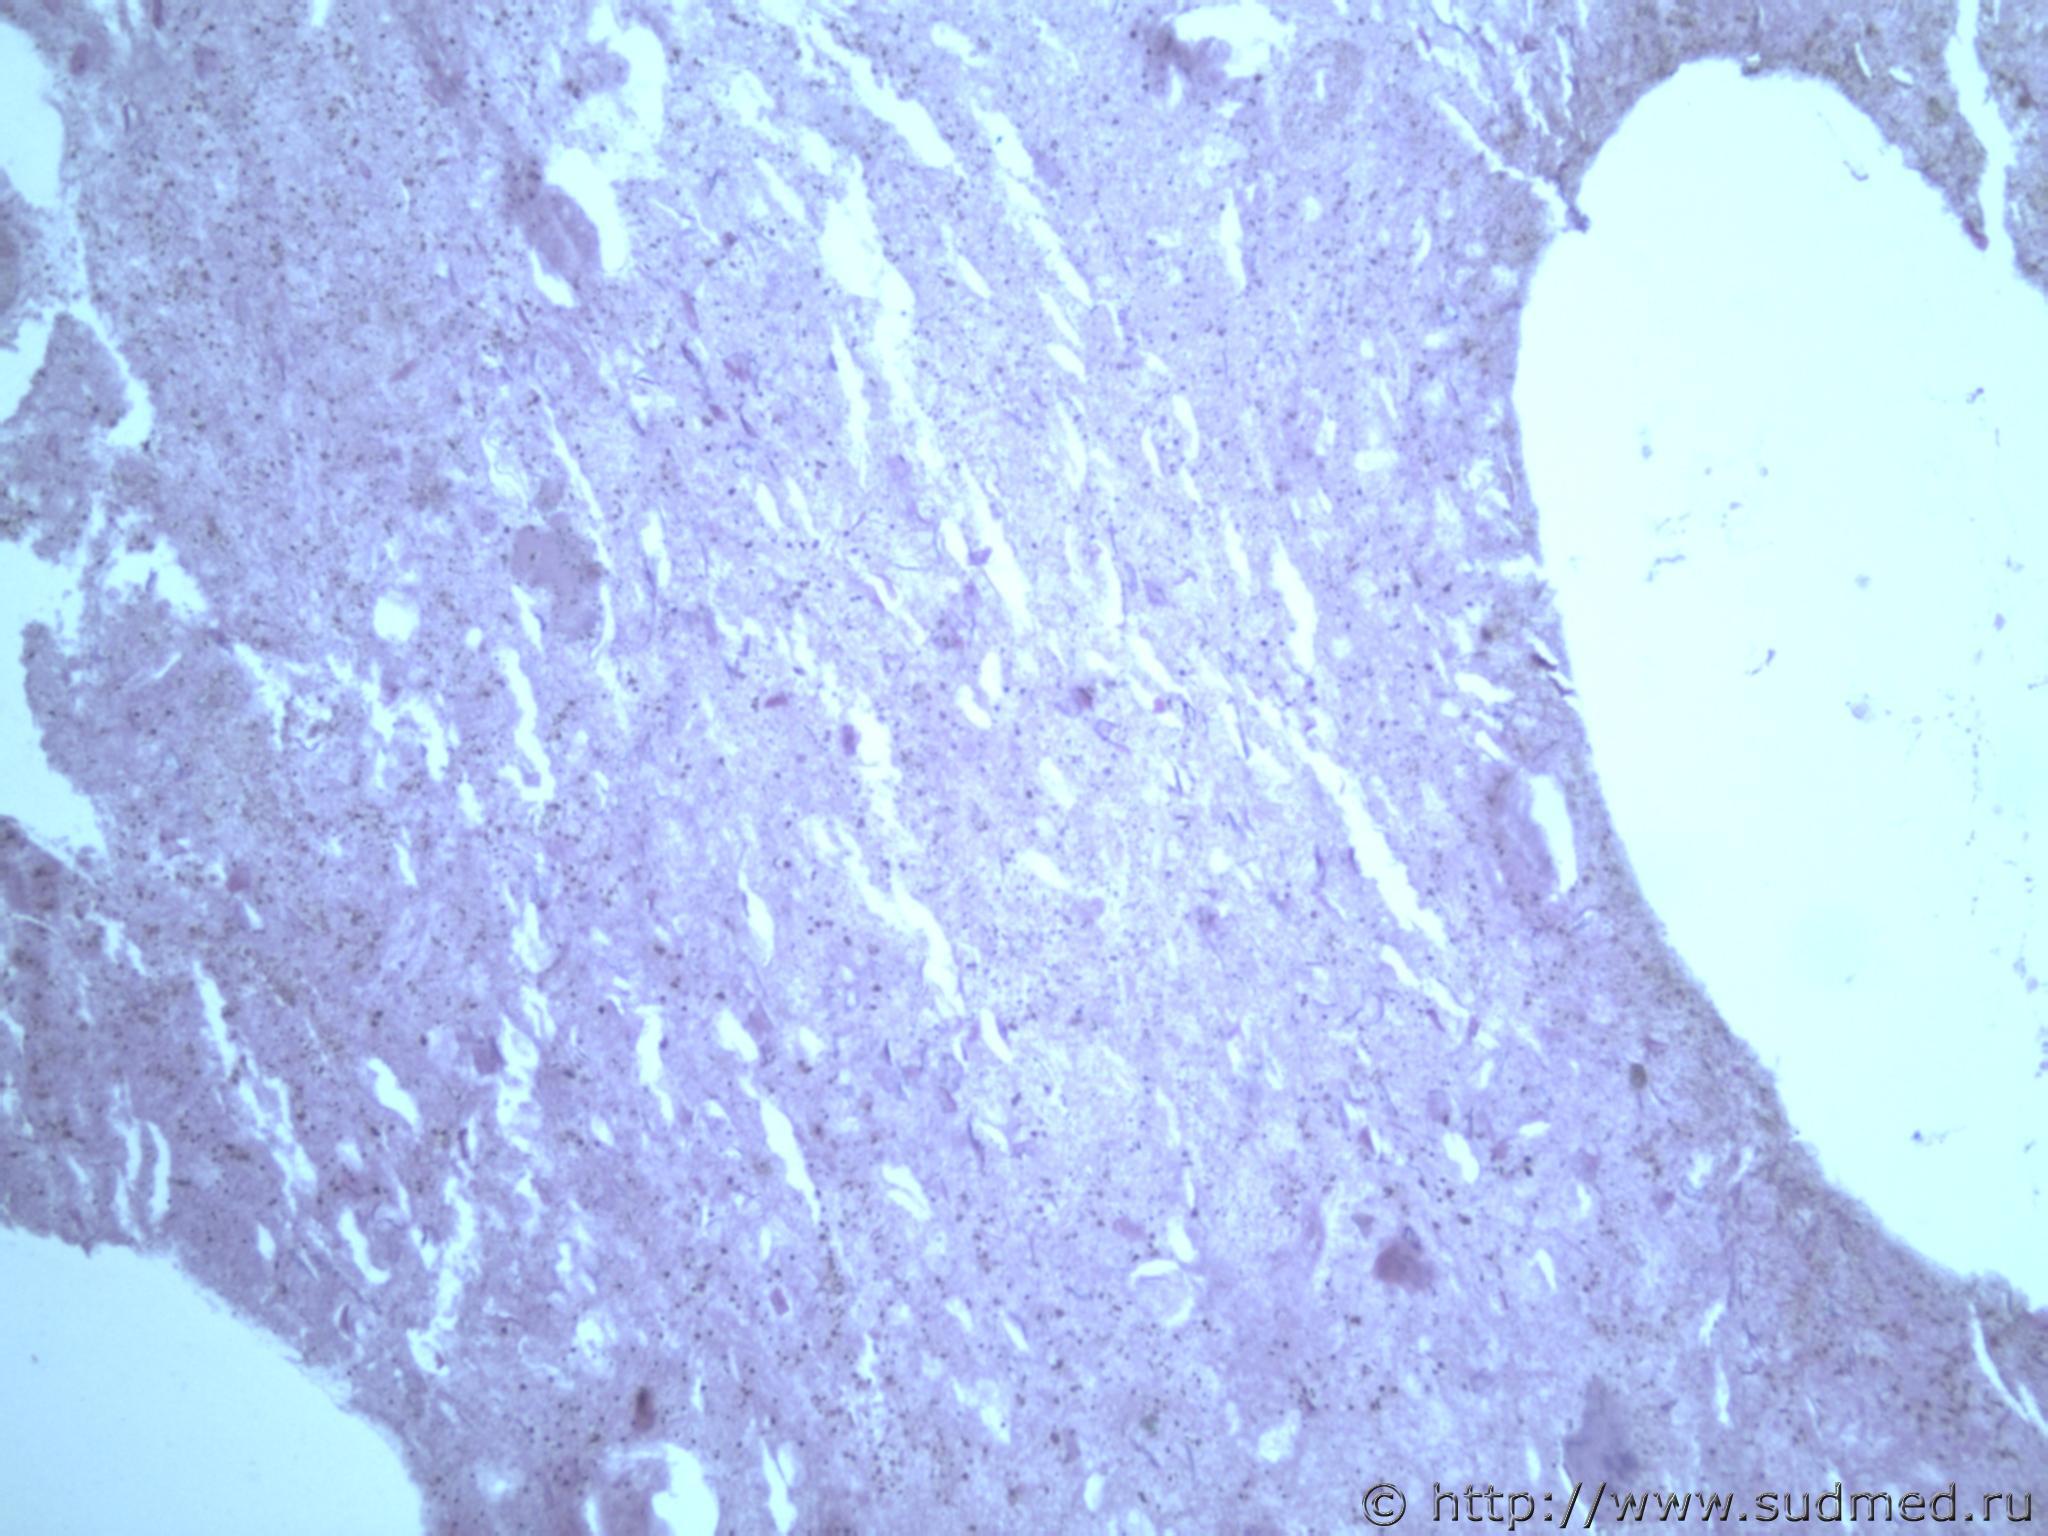

всем здравствуйте. хотела бы знать ваши мнения. провожу экспертизу. препараты как и труп новорожденного гнилые либо в аутолизе страшном. в легком картина такова, что ткань "плотная". просвет различимых альвеол в виде щелей и по всем полям зрения элементы околоплодных вод. одна артерия пуповины спазмирована. остальные сосуды непонятно : просвет их спавшийся но без признаков спазма. они как будто сплющены. да и сама пуповина в виде тонкого тяжа, видно из-за гнилостных изменений. под тмо спинного мозга признаки кровоизлияния, как и в коже с шеи. в коже головы с полнокровием отдельных сосудов. мать утверждает что ребенок после родов не сразу но все же шевелился и кричал. хотя перед этим он выпал у нее из матки на пол, ударившись головой. и со слов матери у него была пена изо рта и он хрипел.

Микрофото лёгких показать можете ?

сегодня сфоткаю конечно. но не факт что будут качественные фотки. плавательная проба - "сомнительная".

Судебная медицина - Прикрепленное изображение Судебная медицина - Прикрепленное изображениеСудебная медицина - Прикрепленное изображениеСудебная медицина - Прикрепленное изображениеСудебная медицина - Прикрепленное изображение

ну вот как то так. там еще и фотки пуповины.

Плохо,материал гнилой.

Остановился бы на дышавшем лёгком.

5 фото в сообщении №4 и 8 фото в сообщении №5 не наводит ли на мысль о дышавшем лёгком ?

Про остальные фото молчу,там или ничего не видно или же есть оптически пустые пузыри,что вероятнее всего,проявления гниения.